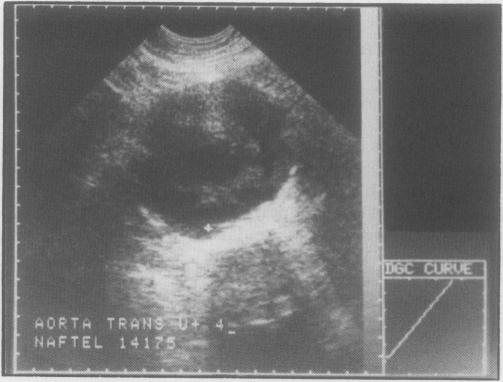

The treatment of abdominal aortic aneurysm has undergone dramatic changes over the last three decades. More sophisticated diagnostic techniques have allowed early elective repair to be carried out. Improvement has resulted in both morbidity and mortality rates. Investigations such as ultrasound, computerized tomographic scanning and arteriography allow easy confirmation of the diagnosis of aortic aneurysms and permit a better assessment of the extent prior to surgical intervention. Improvement in the pre-operative management, particularly in relation to cardiac, renal, and pulmonary disease, has led to greatly improved results. The most important change in surgical technique has been repair of the aneurysm rather than resection. Combined with better post-operative intensive care units, this development has contributed to the improved morbidity and mortality rates. Although the complication rate of elective repair is low, the major cause of death remains myocardial infarction. As a result of all these improvements, indication for repair of abdominal aortic aneurysms has been extended to patients over the age of 80. Following surgical repair, most patients can be expected to return to normal lifestyles and lifespans.

在过去的三十年中,腹主动脉瘤的治疗发生了巨大的变化。更复杂的诊断技术使得早期选择性修复得以进行。这导致发病率和死亡率都有所降低。超声、计算机断层扫描和血管造影等检查可以轻松确认主动脉瘤的诊断,并在手术干预前更好地评估其范围。术前管理的改善,特别是在心脏、肾脏和肺部疾病方面,导致了结果的显著改善。手术技术最重要的变化是修复动脉瘤而不是切除。与更好的术后重症监护病房相结合,这一发展有助于降低发病率和死亡率。尽管选择性修复的并发症发生率较低,但主要的死亡原因仍然是心肌梗死。由于所有这些改进,腹主动脉瘤修复的适应证已扩展到 80 岁以上的患者。手术后,大多数患者可以恢复正常的生活方式和寿命。

Evaluation of aneurysms by computed tomography.通过计算机断层扫描评估动脉瘤。

Surgery. 1981 Feb;89(2):216-23.